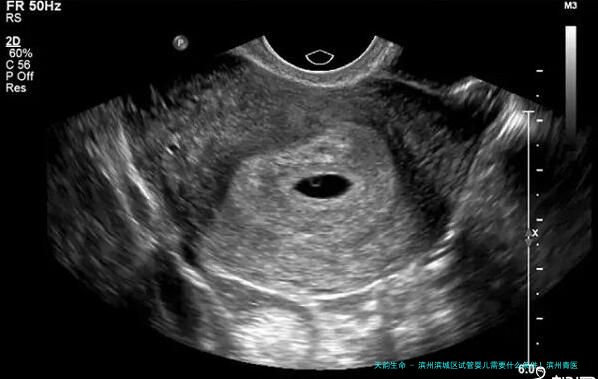

滨州作为一座历史久远文化文化底蕴深沉的城市,近几载来其医疗水平相继提升,吸引了越来越多的求子家庭前来寻求生殖辅助治疗。对于想通过试管婴儿的形式怀上宝宝的家庭来说,了解当地的医院以及相关先决条件极为重要。全体公民健康网将就滨州滨城区试管婴儿所需前提、保举医院及费用情况进行详细介绍,希望能帮助到有须要的人们。

想要在滨州滨市区开展试管婴儿治疗,起先须要满足必须的条件,这一些条件主要包括年龄限制、身体健康状况等方面。一般来说女性申请试管婴儿的年龄范围为23-四十五岁,男性便要在18-60岁之间。同时夫妻双方都须要进行一系列体检和检查,保障身体健康,没有影响生育的严重病症。